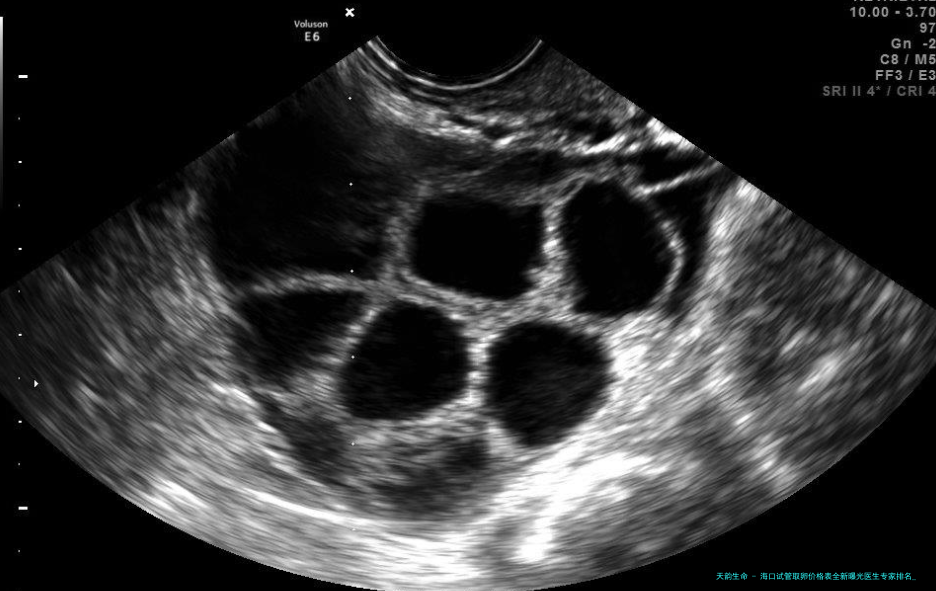

取卵手术本身(约5000-一万五千元):含麻醉、超声疏导穿刺耗材。海口市妇幼保健院引进德国卡尔史托斯内镜系统,精准度提升40。

AI卵泡监测系统在海南医疗学院附属医院试用,通过算法取卵时机,误差从2小时缩至15分钟;